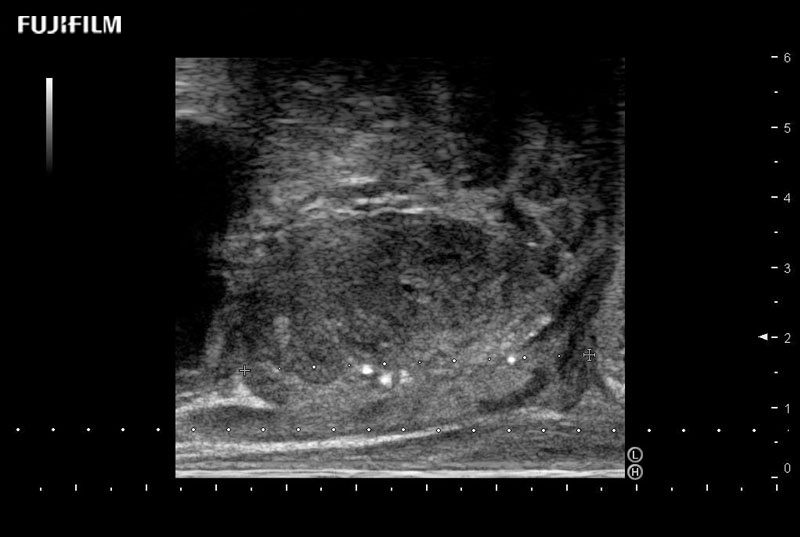

Exclusive 200° FOV end-fire prostate biopsy transducer.

Main Specifications:

Provides real-time imaging of both the sagittal and transverse planes